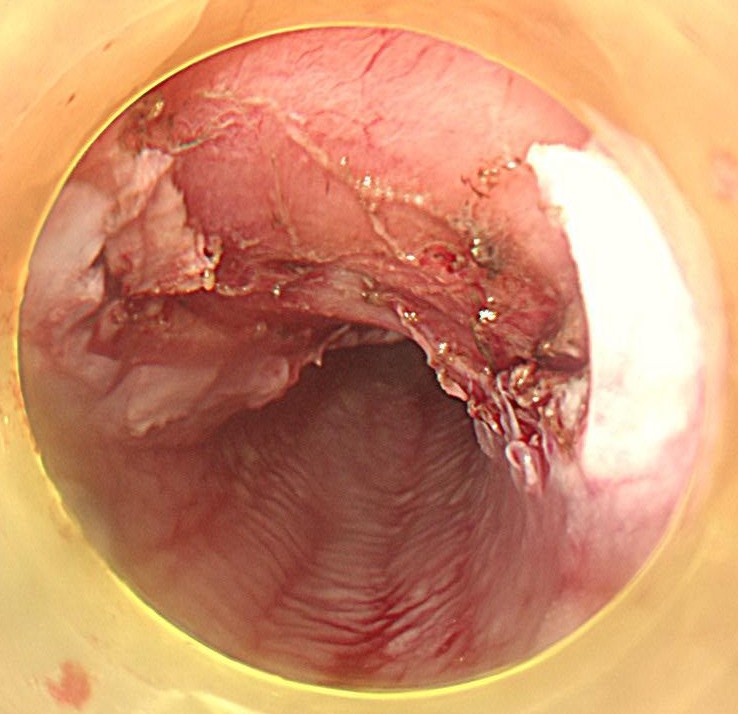

切除終了後の粘膜欠損部です。この後、1か月しっかりと胃薬を飲んでもらいます。

切除後標本です。しっかりと病変が切除できています。病理学的にも根治切除と診断されました。